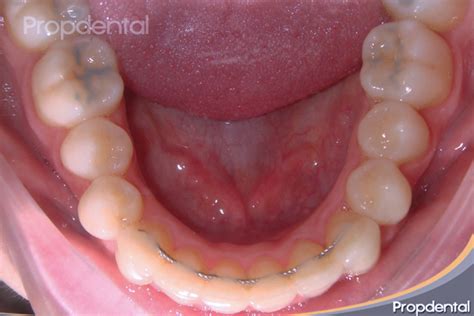

Los retenedores fijos son una excelente opción para evitar movimientos indeseados de los dientes después de la ortodoncia. Se trata de una barra delgada que se adhiere a la cara interna de los dientes, es decir, la parte lingual. Generalmente, se colocan detrás de los cuatro dientes frontales superiores y detrás de los seis dientes frontales inferiores.

Estos retenedores se implantan inmediatamente después de retirar la ortodoncia y se fijan con composite en los incisivos inferiores. Aunque también se pueden colocar en el arco superior, no siempre es posible en todos los casos.

Una de sus principales ventajas es su estética, ya que son prácticamente invisibles al hablar o sonreír.